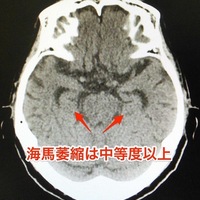

抗認知症薬の脳萎縮予防効果?萎縮を予防したら認知症は予防できる?

ケアネットでみかけたこの記事。 抗認知症薬の脳萎縮予防効果を確認:藤田保健衛生大|医師・医療従事者向け医学情報・医療ニュースならケアネット 果たして脳の萎縮を予防できたら、認知症予防につながるのだろうか?